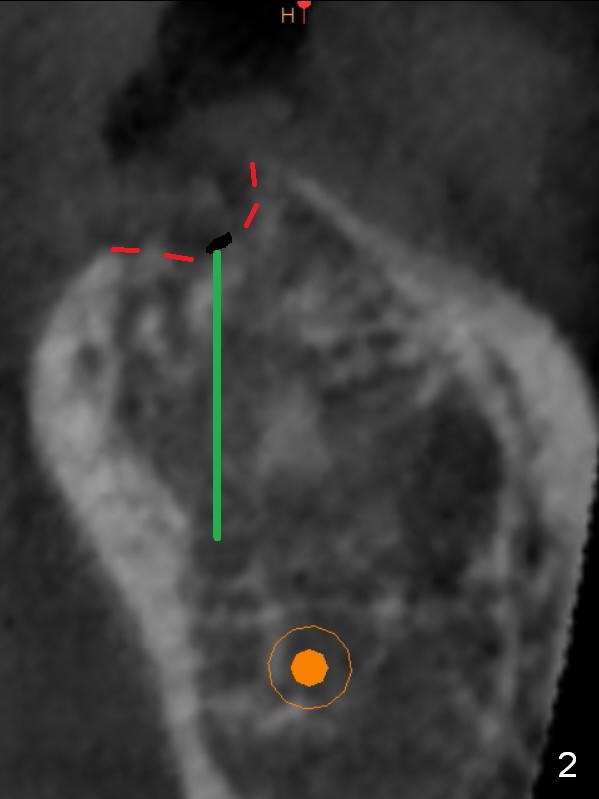

Preop palpation of the edentulous area at #18 does not show the flatness of the ridge top as shown by CBCT.  Incision reveals that the ridge is not as wide as CBCT indicates (Fig.1 (coronal section) between arrowheads).  In fact the ridge is concave (Fig.2 red dashed line).  Osteotomy is initiated in the middle of the concavity (Fig.2 green line) with insertion of 7 mm guide pin (Fig.3).   After removal of the pin, the osteotomy is moved buccally (Fig.4).  After Marking Bur and 4.3 mm Magic Drill, a 5x9 mm IBS implant is placed with 2.8 mm clearance from the Inferior Alveolar Canal (Fig.6).  Following deepening the osteotomy with Final Drill, the implant is placed deeper (Fig.7).  The osteotomy happens to be established in the mesial socket, since the distal socket has not completely healed (Fig.6 yellow dashed line).  Granulation tissue is removed.  Since the lingual crest is lower than the buccal one (Fig.1 B), there is lingual thread exposure after implant placement (Fig.5).  The exposed thread is covered by bone graft (autogenous bone, allograft and Osteogen, Fig.5 pink circles).  Some of the graft is apparently pushed into the distal socket (Fig.7 yellow dashed line) post GBR and suture.  As the implant is placed twice, insertion torque is <10 Ncm (although the implant is stable).  A 5x3 mm healing abutment is placed (Fig.7 H).

To bury the implant evenly, the ridge should be flattened (Fig.8) prior to osteotomy and implant placement (Fig.9) when bone height is sufficient.